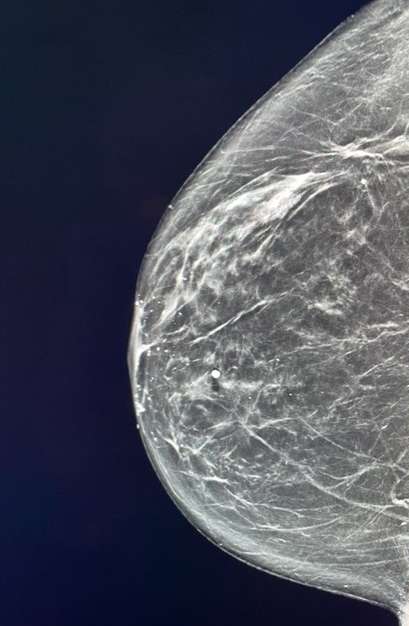

Mammography: Breast lymphomas usually present as a hyperdense solitary oval or round mass. The margins are mostly circumscribed and microlobulated, but can also be indistinct. Though asymmetry, skin thickening, and architectural distortion are quite rare imaging descriptions of lymphomas, they have been reported. Calcifications are almost always absent. Multiple small masses are suggestive of SBL.